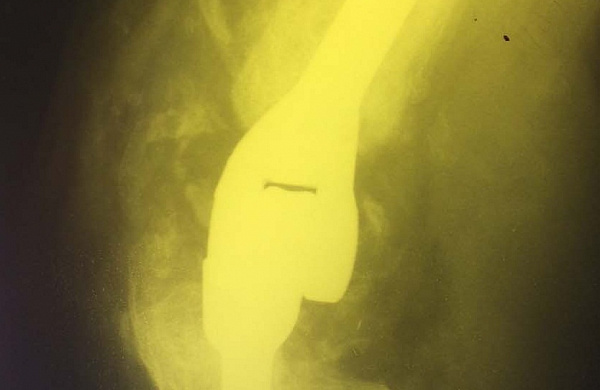

Впервые они осуществили эндопротезирование локтевого сустава. Теперь врачи РКБ умеют протезировать все суставы. Это значит, у пациентов появился реальный шанс вернуть себе радость полноценного движения после самых сложных травм.

В Улан-Удэ впервые провели эндопротезирование локтевого сустава